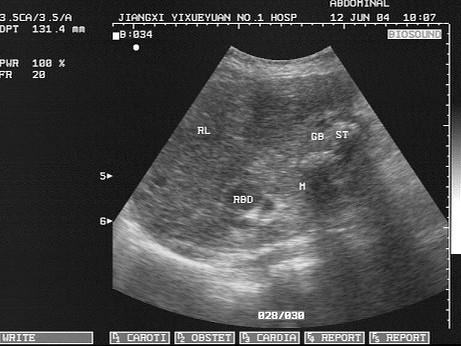

问题 女,47岁,上腹部疼痛十多年,加重2个月余,皮肤巩膜黄染,进行性加重,皮肤搔痒,声像图如图所示(肝内胆管扩张),结合超声声像图,诊断为?(?)

选项 A.肝癌 B.右肾癌 C.胆囊结石并胆囊炎 D.胆囊结石并胆囊癌 E.肝脓肿

答案 D